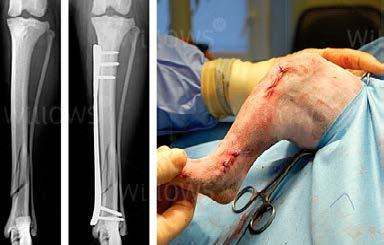

Osteosinteza cu placă minim invazivă (Minimal Invasive Percutaneous OsteosynthesisMIPO) constituie o metodă nouă de fixare cu placă care permite ca placa să fie aplicată prin incizii mici realizate de la distanţă de sediul

fracturii. Această tehnică se supune principiilor de osteosinteză biologică dat fiind faptul că sediul fracturii nu este expus ș i minim afectat. 33 MIPO reprezintă o metodă de osteosinteză utilizată atât în medicina umană, cât și în cea veterinară.

Introducerea percutanată a plăcii elimină necesitatea realizării unui acces chirurgical extins în scopul expunerii sediul fracturii. 53 Fragmentele de os sunt reduse utilizând tehnici de reducere indirecte. 24 Inciziile reduse de inserare a plăcii sunt realizate la fiecare capăt al osului fracturat ș i se crează un tunel epiperiostal care conectează inciziile. Placa este inserată printr-una dintre inciziile de insertie ș i va aluneca prin tunel de-a lungul suprafeţei periostale a osului, acoperind focarul de fractură. Şuruburile sunt aplicate la capetele proximal ș i distal ale plăcii prin inciziile de inserţie sau, dacă este necesar, prin incizii adiţionale obţinute prin străpungere – figura 26.

Figura 26. MIPO într-o fractură de tibie la cîine (Din https://www.willows.uk.net/specialist-services/pet-health-information/orthopaedics/minimally-invasive-fracture-surgery)